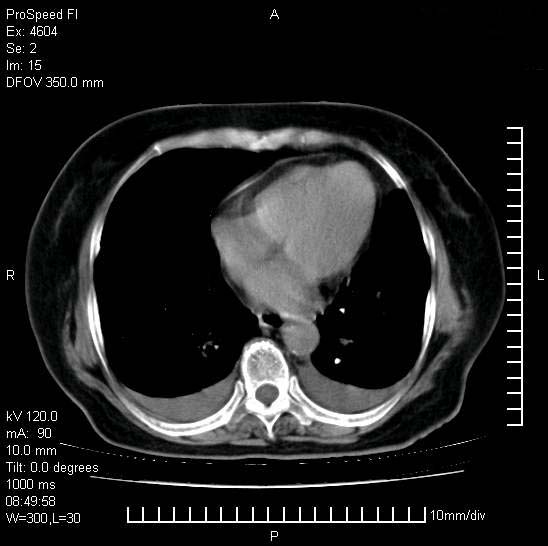

十几年前曾患肺结核,一周前突咳血约100ml,中性粒细胞稍高,诊断两上肺陈旧结核,下肺炎症,给予抗炎治疗,近几日晚上高热,39度,仍咳少量血,4天前ct及今天ct上传。

今天ct

短短几天内,病变范围明显增多扩大,以左侧明显,而且双侧出现胸水,还是考虑感染.

短短几天内,病变范围明显增多扩大,以左侧明显,而且双侧出现胸水,我更多考虑左侧中心性肺癌并并阻塞性不张及肺炎,炎症变化也太快了!